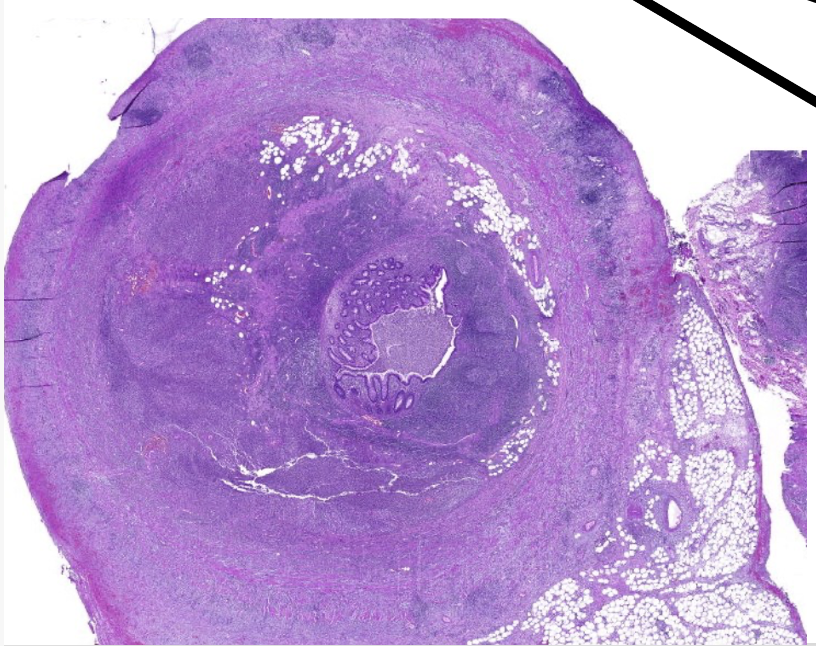

welk orgaan

prostaat hypertrofie

pathologische kenmerken prostaat hypertrofie

ipv lobulaire—> nodulaire indeling, omgeven door bindweefsel

bevat gedilateerde klierbuizen

vorming van cysten (cysteuze dilatatie)

toename stroma, glad spierweefsel en lymfocyten